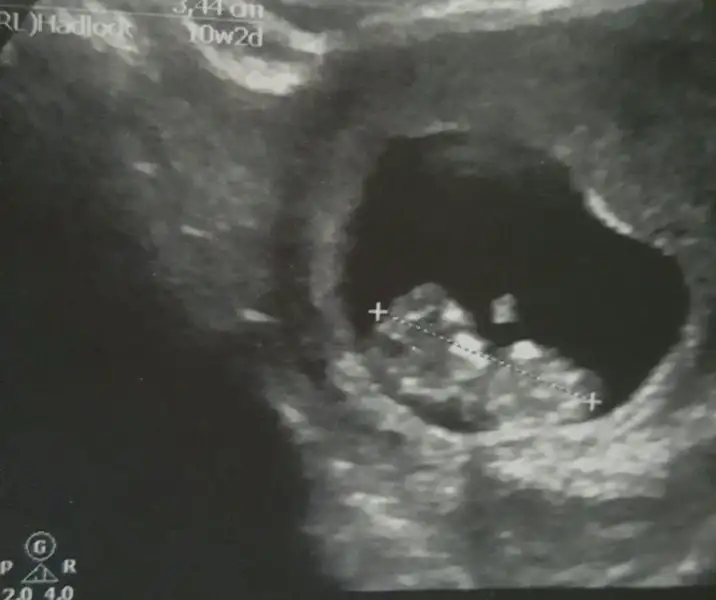

İnşallah canım. Ben de bir kızım olsun çok istiyorum :) Bu usg de şimdiki bebişimin 6+3 günlük karından :)

Eklentiler

• IMG_20151212_171135.webp

IMG_20151212_171135.webp

17,3 KB · Görüntüleme: 253